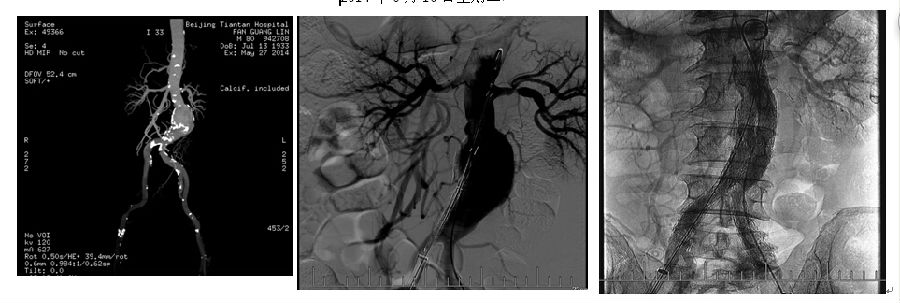

2014年6月6日我院普通外科血管专业组贾玉龙主任医师、汪岩副主任医师及史敬东主治医师等成功的为一八十岁高龄合并有高血压、糖尿病的男性患者在导管室完成了腹主动脉瘤腔内隔绝术。术后患者恢复良好,已顺利出院。这是我院首例并且是独立完成的大动脉腔内手术。

腹主动脉瘤好发于老龄人群,一旦出现,就会向着破裂的方向不断进展,故一经诊断即应给予高度重视并尽早采取相应治疗。目前,常用治疗动脉瘤的方法是传统开放手术和腔内隔绝术治疗。开放手术切口巨大,出血多,创伤大,死亡率和术后并发症发生率较高,多数高龄患者不能耐受此种疗法。而微创的腔内隔绝术与传统的开腹手术相比,手术创伤大大减小,手术时间大大缩短,术后恢复快,并发症及死亡率明显降低,使许多不能耐受传统手术的患者获得了治愈机会。